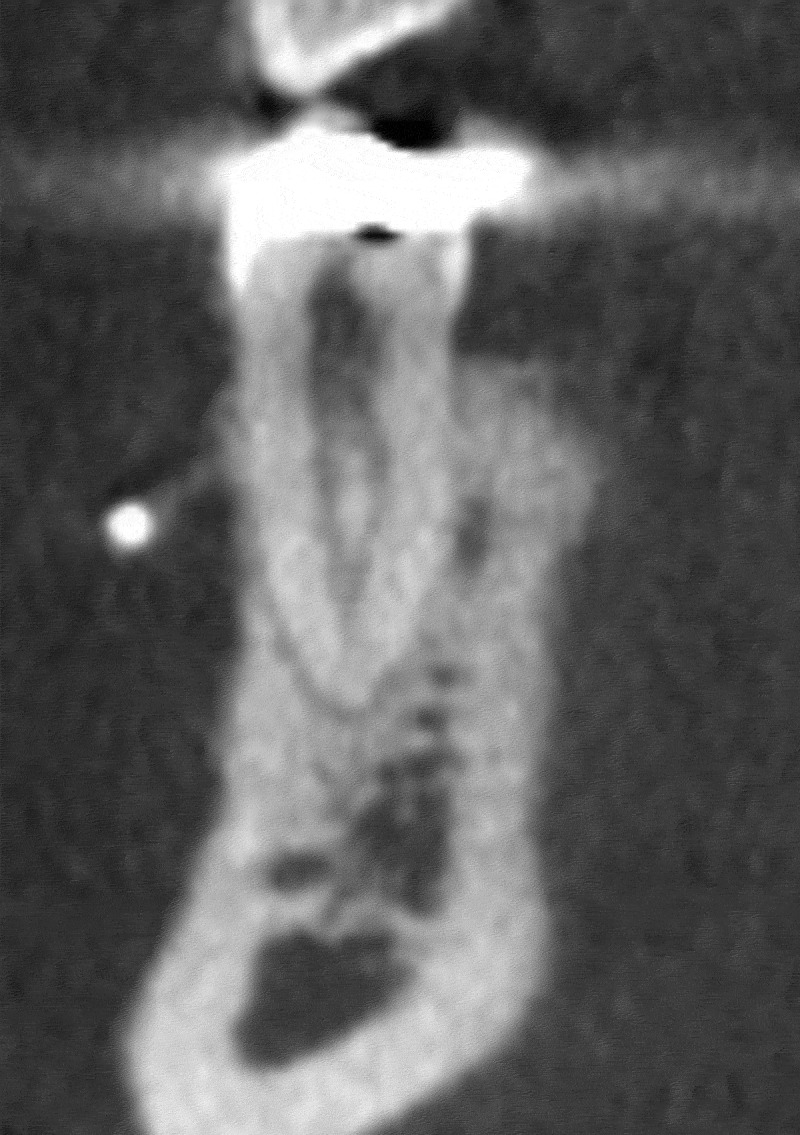

In-depth knowledge of the anatomical structure of the root canal system is fundamental for successful endodontic treatment. This research aimed to evaluate the root canal structures of lower premolars in the Saudi western demographic via Cone Beam Computed Tomography (CBCT) scans. 760 CBCT scans were reviewed, which incorporated 2747 mandibular premolar teeth. SPSS was employed for descriptive statistics and Pearson chi-square tests. The Kappa tests were executed for intra- and inter-observer consistency. The number of roots, canals, and canal configurations based on Vertucci's classification were assessed. The study further explored the prevalence, patterns, and variations of the root canal systems, considering gender-based variations and bilateral resemblance. Predominantly, mandibular premolars possessed a single root, though a minority displayed two or three roots. The occurrence of multiple canals was also on the lower side, with the type I canal pattern emerging predominantly. Gender-based distinctions were evident, as males exhibited a higher frequency of two-rooted premolars and multiple canals than females. It was noted that the anatomical differences were more in the mandibular first premolars than in the second premolars. A significant bilateral consistency was observed, with most teeth showcasing consistent root and canal numbers. This research offers essential perspectives on the diverse nature and variability of root canal anatomy within the Saudi Western cohort, facilitating better understanding and treatment planning in endodontics.

Abstract Image